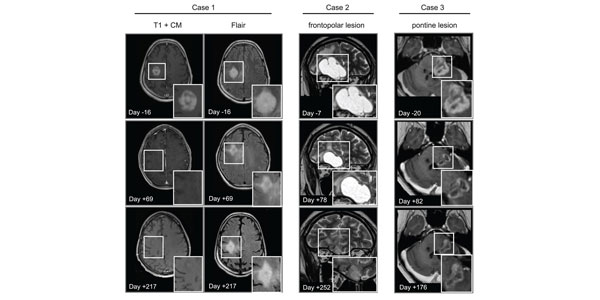

These representative MRIs of responding patients show tumors shrinking throughout the course of avapritinib therapy.

Scientists from an international team that includes the Chavez lab at Sanford Burnham Prebys and many other institutions published findings in Cancer Cell showing that the drug avapritinib may be effective against certain brain tumor cells. Notably, the drug was found to be one of the rare few that can cross the blood-brain barrier known to prevent the passage of more than 98% of small molecule drugs.

Avapritinib is approved by the Food and Drug Administration for treating gastrointestinal and other cancers. With more research, it may be possible to repurpose avapritinib to treat high-grade gliomas.